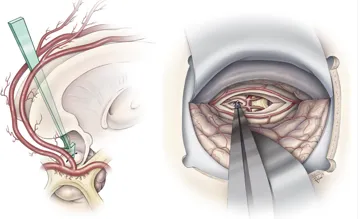

在颅咽管瘤术前评估中,需要重点考虑肿瘤的主要位置(交叉前区、鞍后区、交叉后区)以及肿瘤与视交叉、下丘脑附着的关系,垂体漏斗和垂体柄的位置。体积较大、结构复杂的肿瘤可能需要联合不同手术入路。

颅咽管瘤手术的首要目标是安全、彻底地切除肿瘤,其次要尽可能保留垂体柄功能。重点保护这些结构的原因在于它们对患儿未来生活质量至关重要。垂体柄参与激素分泌调节,下丘脑则像汽车的刹车和油门系统,负责调控激素分泌的节律。

此外,手术必须在保护视神经等重要结构的前提下,尽可能实现肿瘤全切除,以预防复发。对于颅咽管瘤手术而言,保护垂体柄和视神经功能的完整性是主要目标,若能在这一前提下实现完全切除,则达到理想的手术效果。